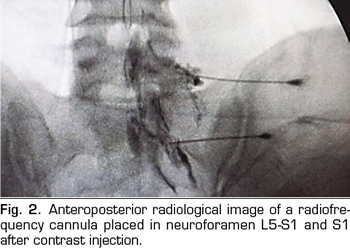

Figure 2